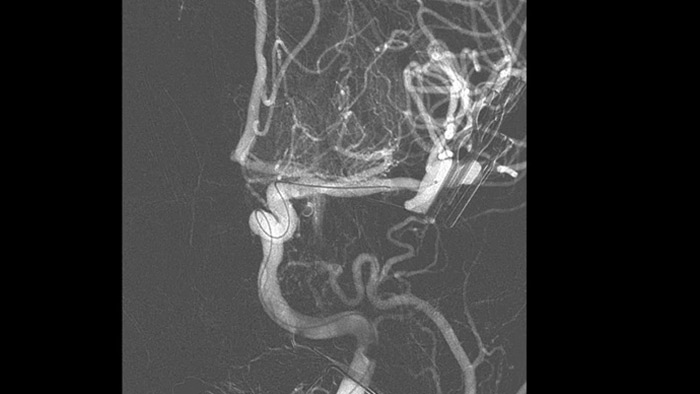

SmartCT Vaso позволяет проводить визуализацию за пределами тромба с помощью перипроцедурного создания изображений дистальных сосудов при ишемическом инсульте. SmartCT Vaso — это метод сбора данных, основанный на получении КТ-изображений с помощью конического пучка и внутриартериальной инъекции контраста. Технология позволяет проводить визуализацию за пределами тромба с помощью перипроцедурного создания изображений дистальных сосудов при ишемическом инсульте. При ретроградном наполнении становится видна структура сосудов до и после тромба. 3D-схема сосудов SmartCT Vaso может использоваться при визуализации устройств для извлечения тромба.

Высококачественная визуализация в режиме DSA позволяет оценить, был ли тромб полностью удален и произошло ли растворение сгустков крови в головном мозге. Врачам предоставляется возможность проверить восстановление кровотока в области ишемической полутени, а также наличие кровотечений в периоперационный период.

Принимайте обоснованные решения о том, можно ли добраться до сгустка и какой путь использовать. Технология Roadmap Pro, усовершенствованная схема сосудов с двойным контрастом, помогает улучшить визуализацию перекрывающихся сосудов, сохраняя при этом баланс дозовой нагрузки.